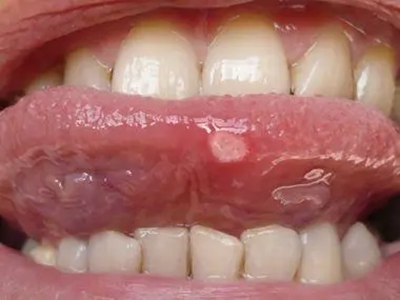

舌头

溃疡 · 白斑

溃疡性口炎舌头上有两个白圈图

溃疡性口炎舌头明显红肿,其上有白斑,类似白圈一样,能多发或单发,部分相互融合,能形成较大的创面,患者有明显疼痛感,进食时疼痛更加明显。